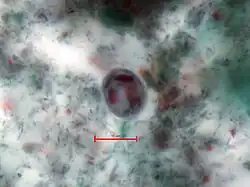

Merkmale

Entamoeba histolytica ist ein einzelliger eukaryoter Organismus ohne Mitochondrien (stattdessen mit Mitosomen), lebt anaerob, ernährt sich heterotroph und ist zur Phagozytose anderer Zellen, beispielsweise von Bakterien, fähig. Wegen seiner wandelbaren Körperform, verbunden mit einer Fortbewegung über Pseudopodien (Scheinfüßchen), wird er – wie auch verschiedene andere Arten – als Amöbe bezeichnet. Dieser amöboide Protist gehört zur Gattung Entamoeba. E. histolytica durchläuft in ihrem Lebenszyklus zwei Stadien: das einer unbeweglichen Zyste und das eines Trophozoiten, der hauptsächlich den menschlichen Darmtrakt besiedelt. Die Minuta-Form des Einzellers wird 10 bis 15 Mikrometer groß, die Magna-Form 25 bis 40 Mikrometer. Die gebildeten Zysten sind tetraploid, sie enthalten im reifen Zustand vier Zellkerne und erreichen eine Größe von rund 20 Mikrometern.[1]

Trophozoit, E. histolytica

Trophozoit, E. histolytica -

Trophozoit, E. histolytica

Trophozoit, E. histolytica -